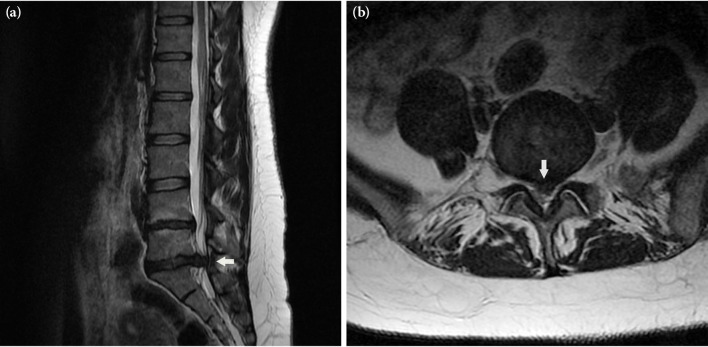

在这个病例报告中,我们介绍了一位38岁的女性患者,她因腰椎操作治疗腰椎间盘突出症而出现马尾综合征。目的是讨论马尾综合征后康复的结果,以及与之相关的挑战。尽管在康复过程中遇到了困难,但一个全面的多学科康复计划对于马尾综合征患者获得独立性和恢复日常活动、社交生活和工作是有益的。

In this case report, the rehabilitation process of a 38-year-old female patient who developed cauda equina syndrome due to spinal manipulation for the treatment of lumbar disc herniation was presented. The aim was to discuss the outcomes of rehabilitation after cauda equina syndrome, as well as the challenges associated with it. Despite the difficulties experienced during the rehabilitation process, a comprehensive multidisciplinary rehabilitation program is beneficial in terms of gaining independence and returning to daily activities, social life, and work for patients with cauda equina syndrome.